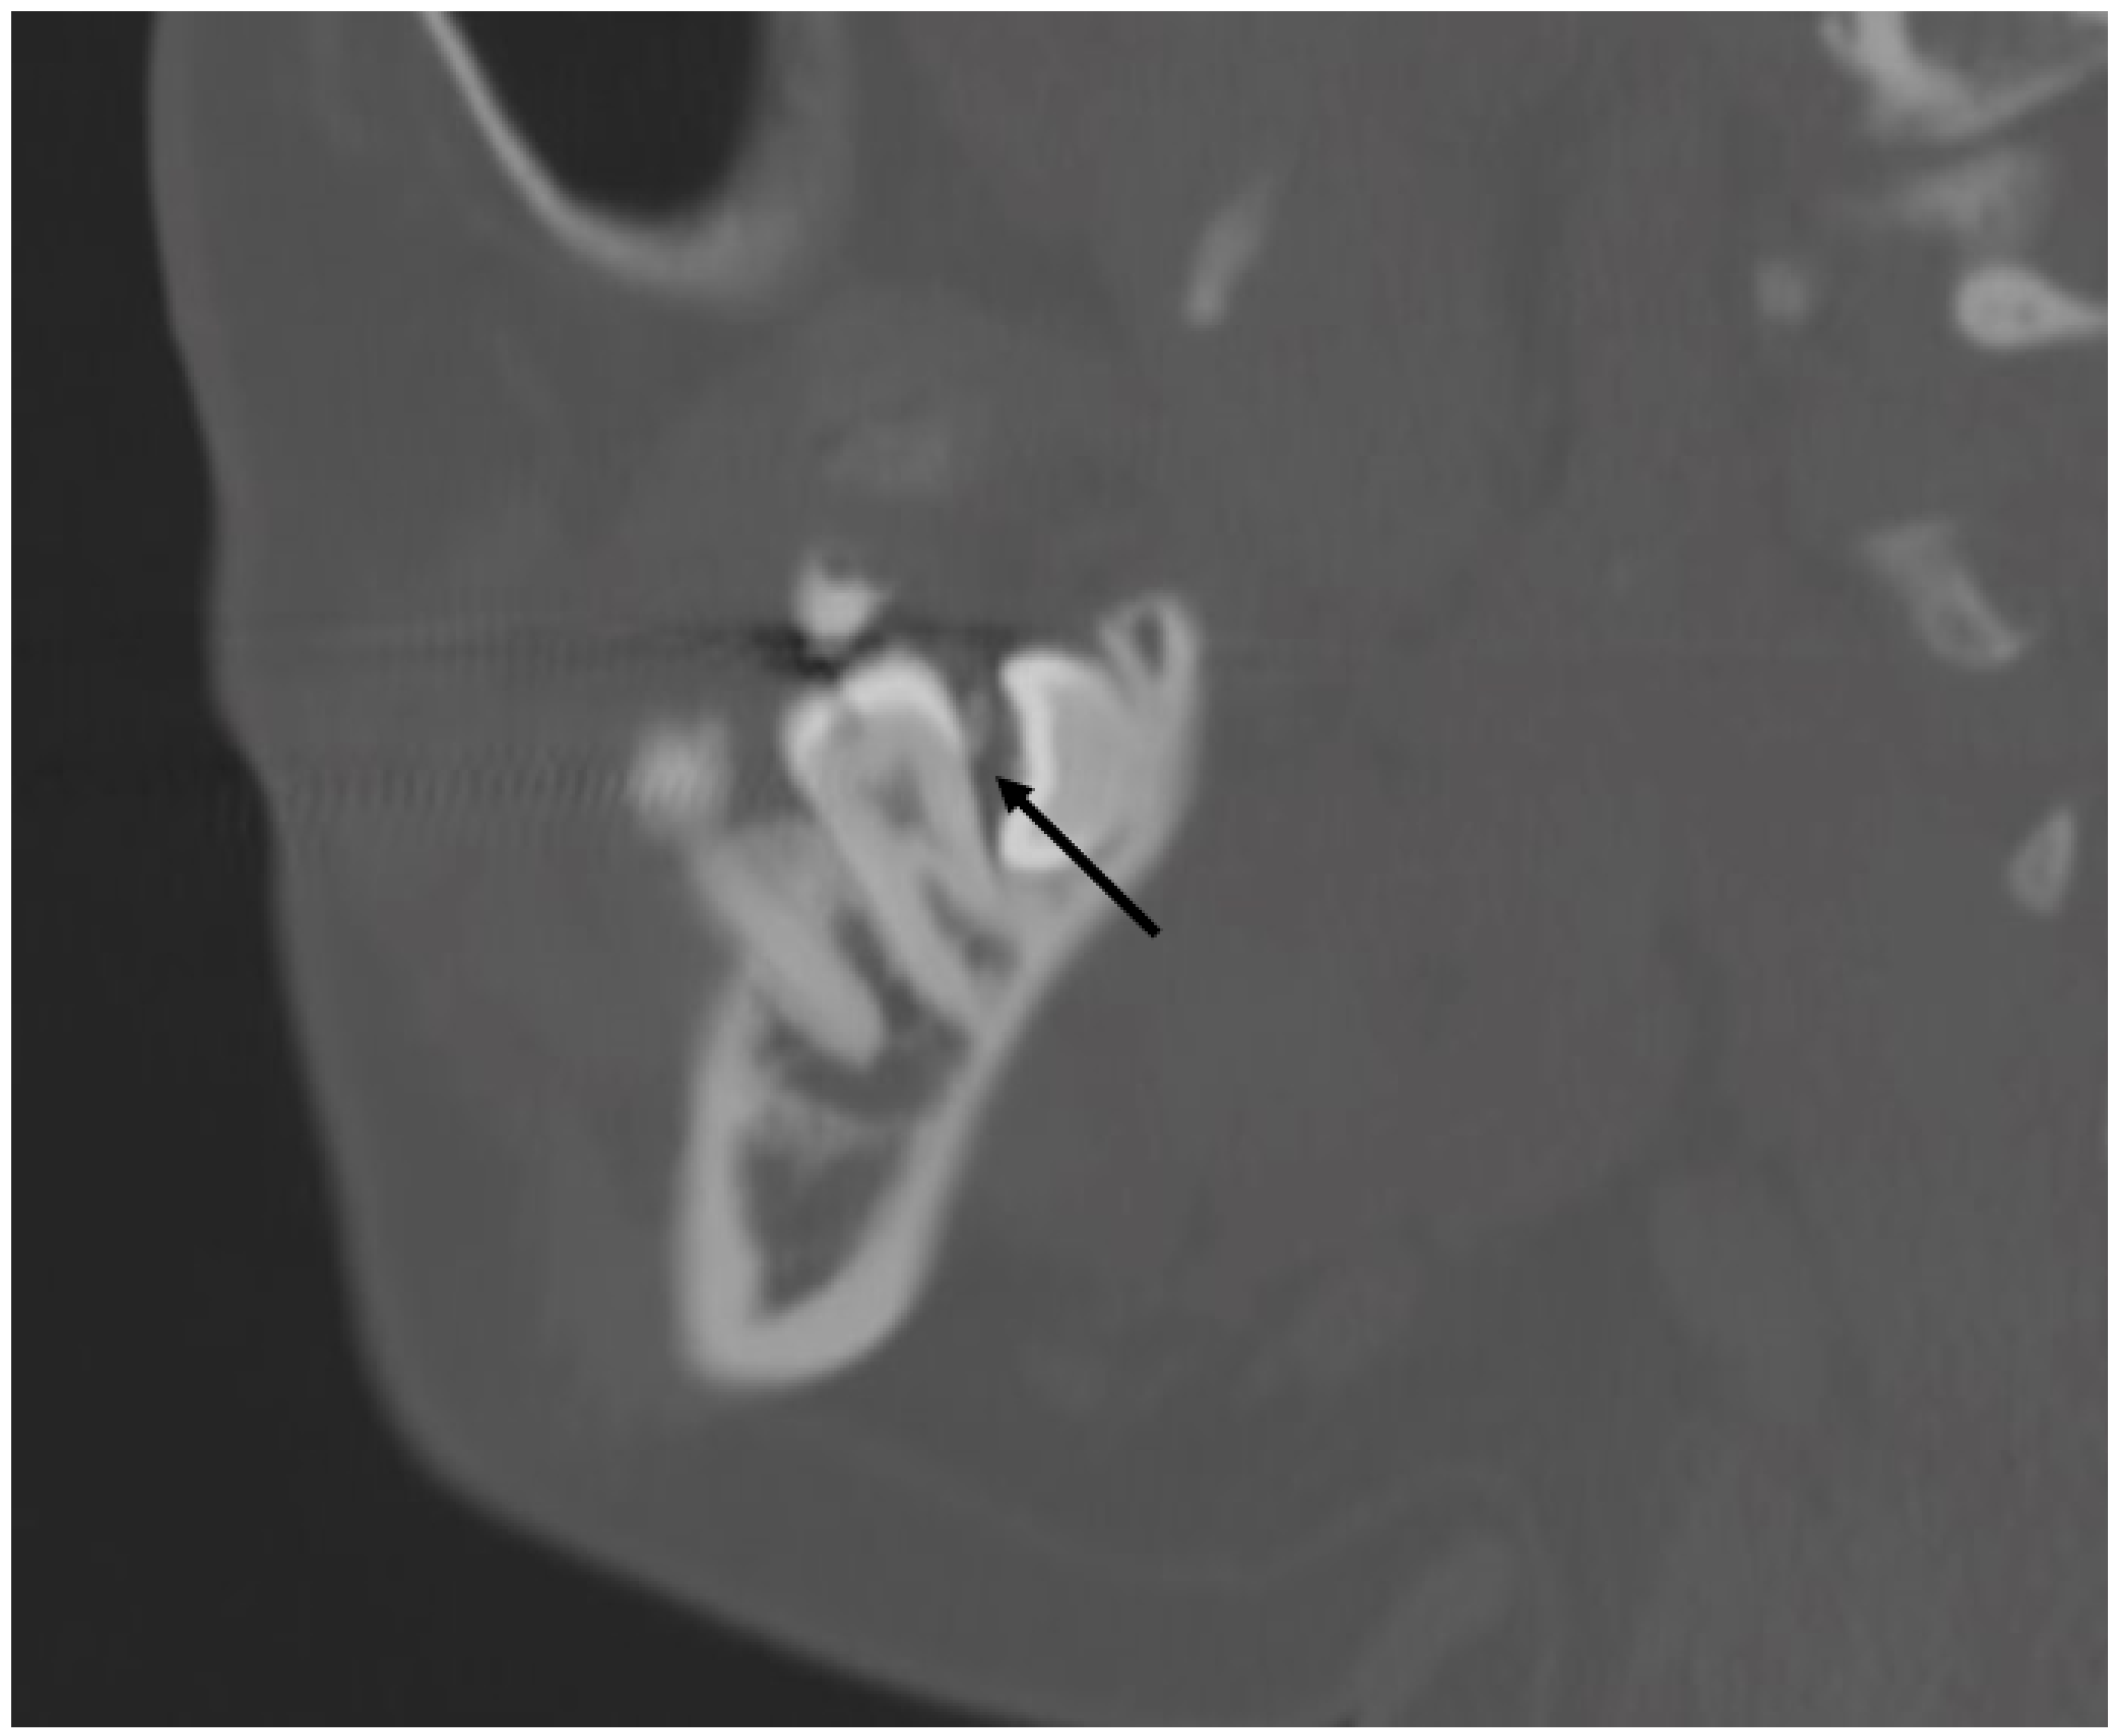

3.5. Anatomical and Imaging Correlations to Odontogenic Infectious Disease

3.5.2. Dental Decay Radiologic Correlations

3.5.4. Periodontal Disease Radiologic Correlations